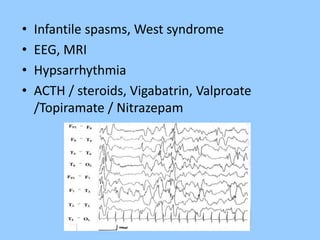

1. The document discusses EEG patterns and findings in various neurological conditions seen in children. It includes descriptions of normal EEG findings as well as abnormal patterns seen in conditions like absence seizures, West syndrome, benign childhood epilepsy with centrotemporal spikes, Lennox-Gastaut syndrome, non-convulsive status epilepticus, subacute sclerosing panencephalitis, and herpes encephalitis.

2. Case studies are presented with clinical histories and EEG findings to illustrate different pathologies. Treatment options are also mentioned for many of the conditions.